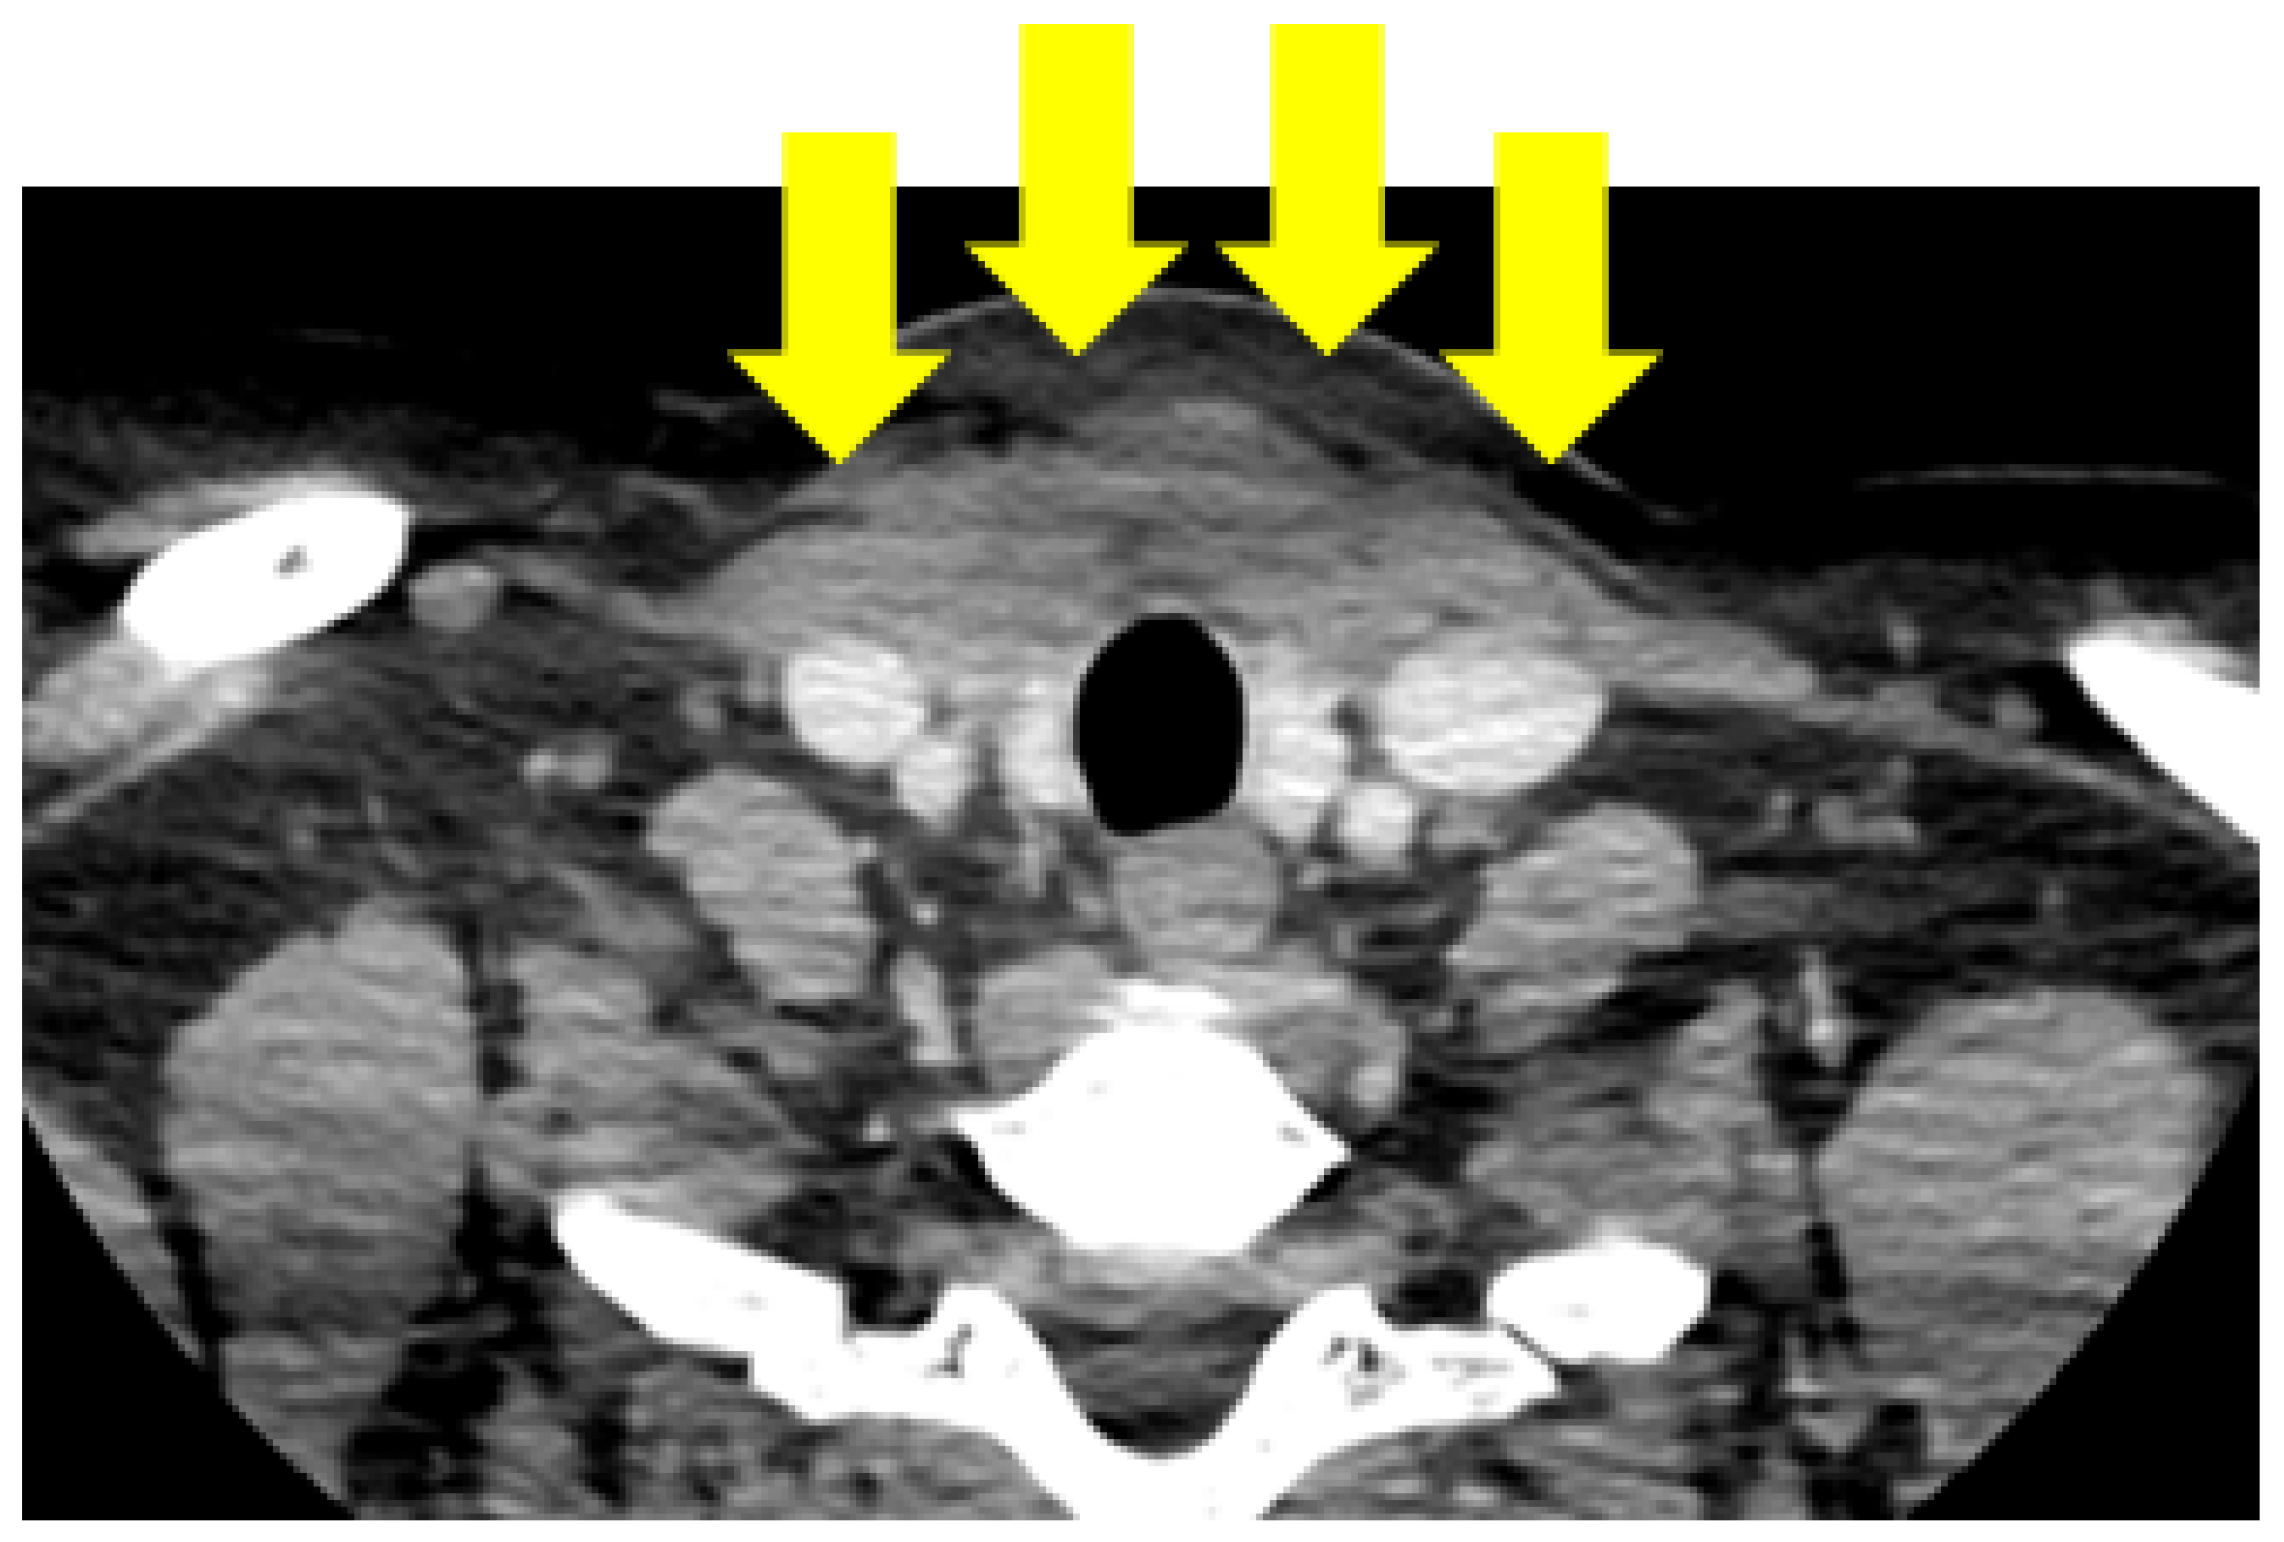

4.1.2. Initial Thyroidectomy and Removal of the Ectopic Thyroid Tissue

4.1.3. Post-Operatory Assessments